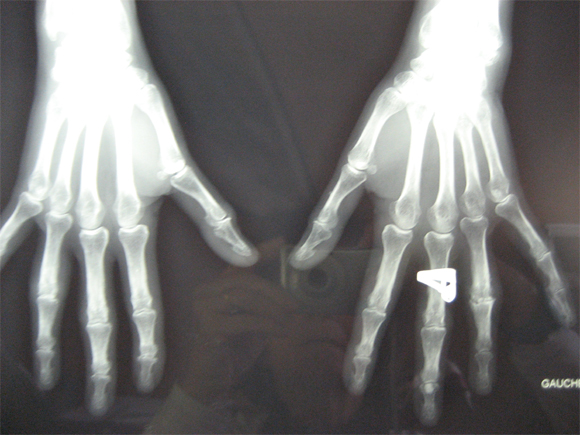

Cas clinique N°48

Dr Véra Lemaire Paris

Il s'agit d'une patiente âgée de 52 ans qui consulte pour une gêne douloureuse des doigts avec une raideur douloureuse matinale d'une demi-heure et un gonflement de l'articulation interphalangienne proximale de l'annulaire gauche.

Elle est également gênée par la même articulation à droite.

Elle n'a aucun autre signe mais signale avoir eu un psoriasis cutané il y a 2 ans qui n'existe plus.

La vs est à 15 mm à la 1ère heure, la CRP à 2. Il n'y a pas de facteur rhumatoïde, pas de facteurs anti-nucléaires, la recherche d'HLAB27 est négative.